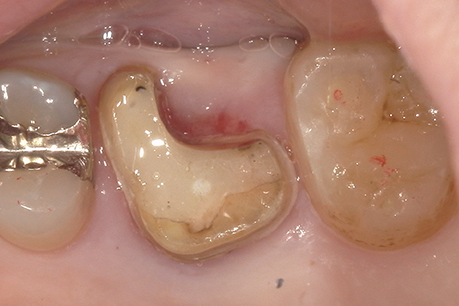

左上6番目

治療の内容:パーフォレーションにより根分岐部病変があり、根尖病変もある症例。歯内歯周病変で歯周病と根尖病変が合併している難治症例。根管治療後分岐部病変が治らなかったため遠心頬側根の歯根切除を行いその後近心頬側根が石灰化しておりそこの根尖病変も治癒が悪かったため歯根端切除も行った。歯周ポケットがなくなり、根尖病変も治癒傾向なため補綴処置を行なった。

治療の期間:8か月

回数:根管治療4回、コア1回、歯根切除1回、抜糸1回、歯根端切除1回、抜糸1回

金額:保険治療

治療のリスク・副作用:術後に歯根破折を起こしたり、清掃不良から歯周病や虫歯を作ることがある。